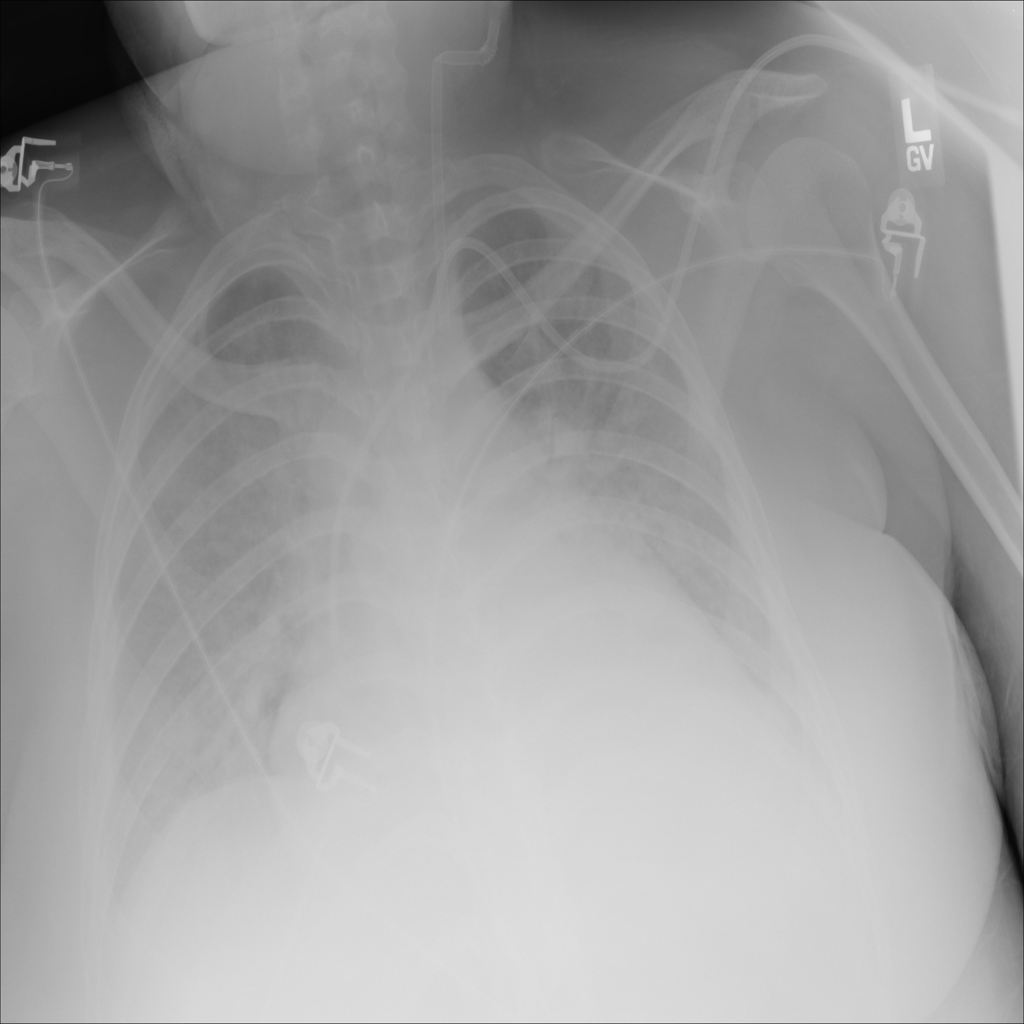

PAT-E828 · IMG-004Edema

PAT-E828 · IMG-004

AP